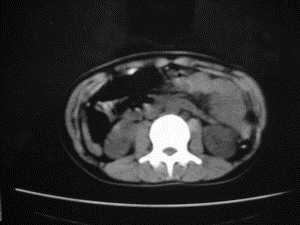

患者女,20岁,被车撞伤3小时,pe:全腹肌紧张,压痛反跳痛,以右上腹为著,肠鸣音减弱。有手术结果。![]() ![]() ![]() ![]() ![]() ![]() ![]() ![]() ![]() ![]() ![]() ![]() ![]() ![]() ![]() ![]() ![]() ![]() ![]() ![]() ![]() jiajie发言: ![]() 考虑空腔脏器穿孔。 dyqct发言:考虑:1、肝左叶外侧段断裂伤伴少量腹血。2、空腔脏器穿孔。 fangzheng发言:仅见腹腔内游离气体,提示空腔脏器穿孔。 guoke发言:胃内密度增高,肠腔内充满气体,考虑肠腔破裂出血 mmg94发言:胃后壁见一增厚软组织密度影,肝左叶前见游离气体影,左腹腔内局部肠管壁、系膜增厚。并见类圆形软组织。以上征象提示消化道管腔破裂,小肠、肠系膜挫裂伤,腹腔血肿形成。 拾荒者发言:肝实质密度不均匀,胃内见不均匀高密度影。考虑:肝挫裂伤,胃内应激性溃疡出血。 守望可可西里发言: 以下是引用jiajie在2006-6-20 15:49:00的发言:[br] [br][br]考虑空腔脏器穿孔。jiajie老师,我鼓起了很大的勇气才决定给您唱个反调儿,如果我错了,请您一定给我指出来,谢谢您了。我反复看了解剖图谱,觉得您所说的“考虑空腔脏器穿孔”上图所用箭头标明的不是游离气体。请您看以下几幅图片: ![]() ![]() ![]() ![]() ![]() ![]() ![]() ![]() 再请您看向医生老师发表的解剖图谱3幅 ![]() ![]() ![]() 这以下几幅图,我认为是肝包膜下积血。不过,说实在话,我没有发现有明显的肝挫裂伤。不对的地方请您一定指出来,再次感谢您了,jiajie 老师! ![]() ![]() ![]() ![]() 这下面几幅图片,我认为有明显的左中上腹部小肠损伤。 ![]() ![]() ![]() ![]() ![]() ![]() ![]() ![]() jiajie 老师,估计我说的是错误的,但我实在闹不明白,请您一定不要笑话我,并指出我的错误,以便于我减少工作中的失误。再次感谢您了,jiajie 老师! 至于胃内的不均匀高密度,我认为拾荒者战友说的有道理,胃内应激性溃疡出血和胃内容物混合所致。 手术结果:左肝叶(iv段)前缘长约8cm挫裂伤口,舌叶根部下< |